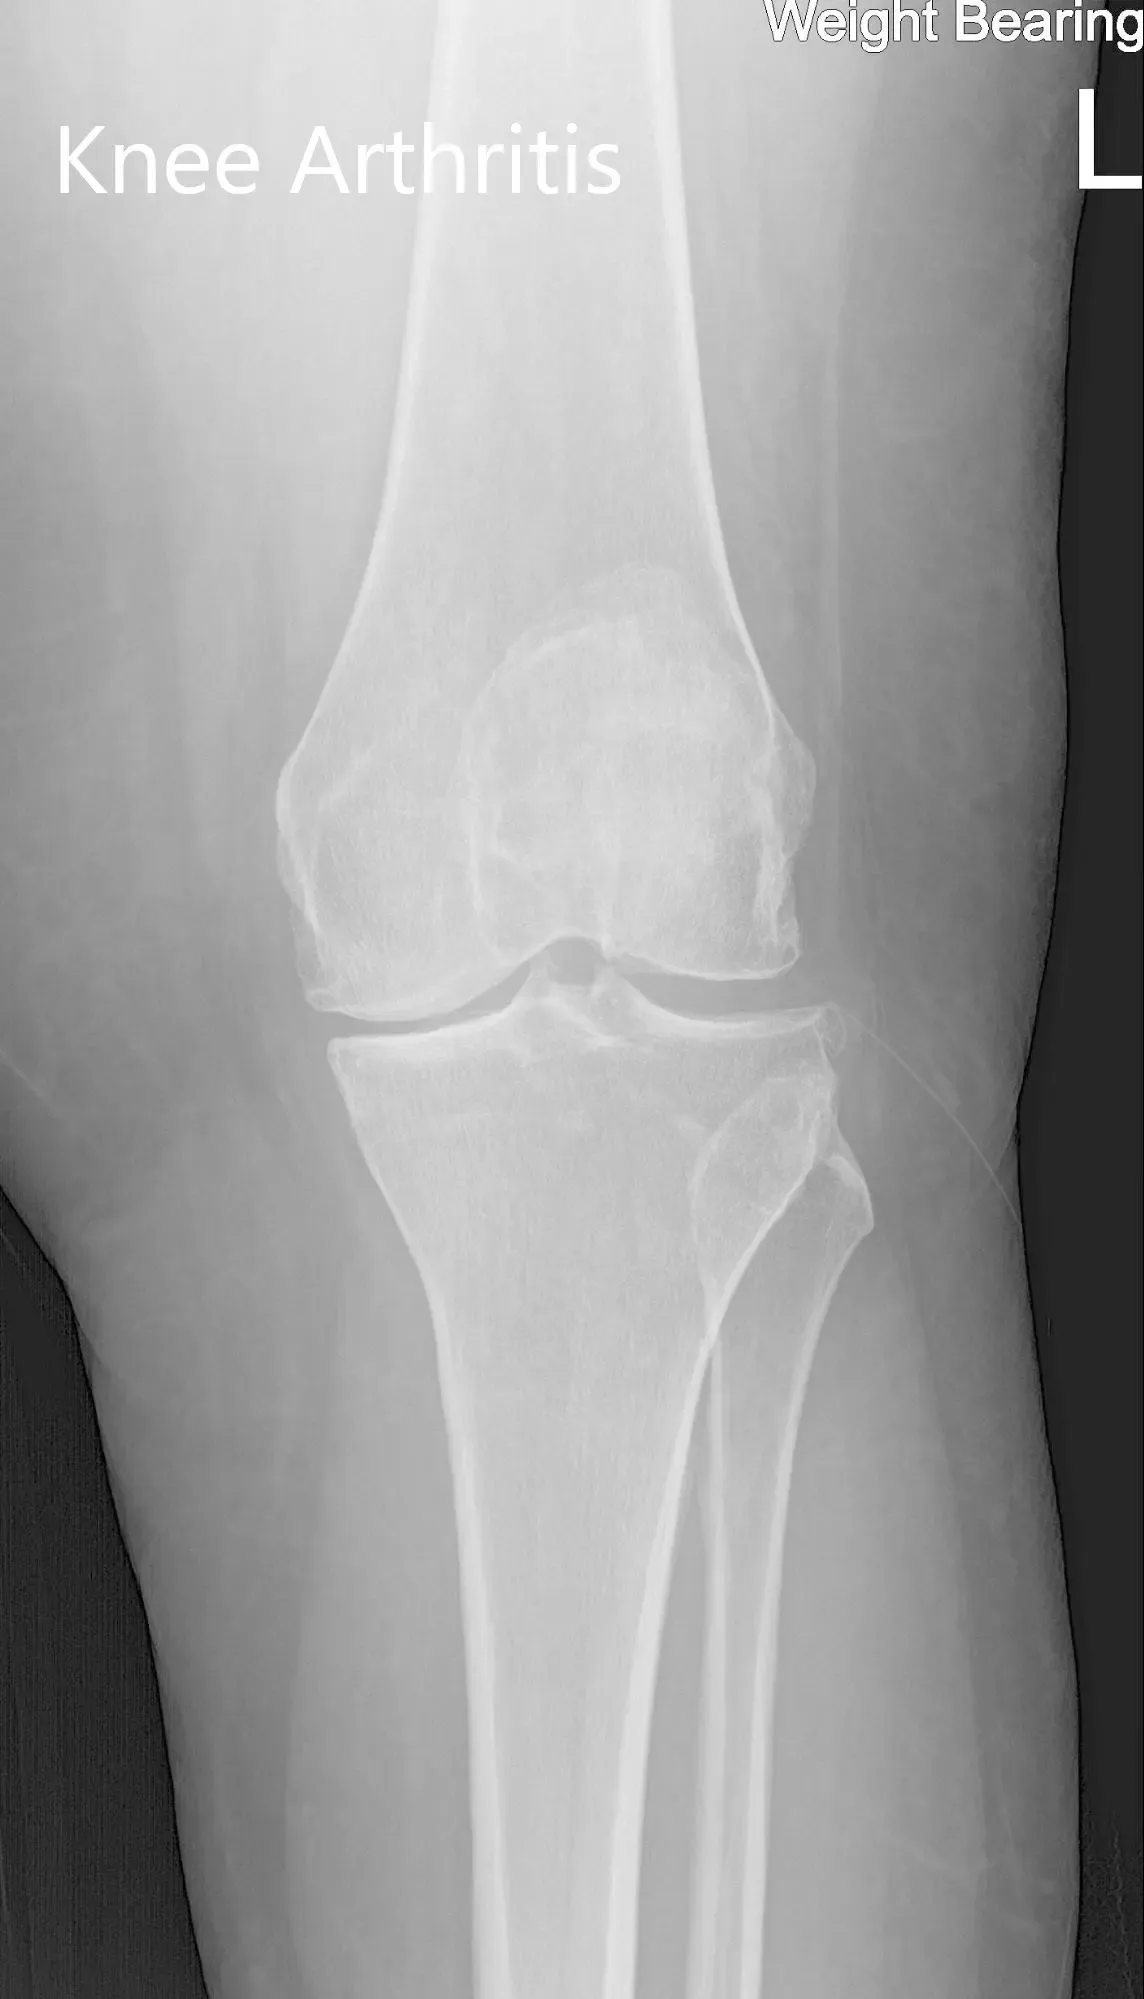

His imaging studies revealed osteoarthritic changes in the left knee. After careful consideration of lifestyle limiting knee pain and his medical condition, he was advised a custom left knee total replacement. Risks, benefits and alternatives were discussed at length with him. He was motivated to get back to his daily routine without knee pain.

Preoperative X-ray of the left knee showing AP and lateral views